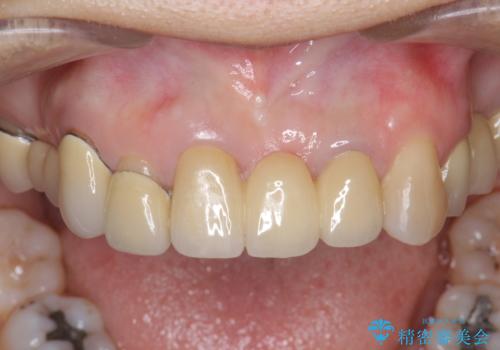

前歯ブリッジのやりかえ

- 前歯の審美障害、見た目の改善を希望され来院されました。

歯肉縁下カリエスも認められるため、挺出を行いセラミックブリッジを審美的に新製します。

- 47万円(仮歯×3・ファイバーコア×2・ジルコニアクラウン×3 歯の挺出)費用は治療当時の料金となります